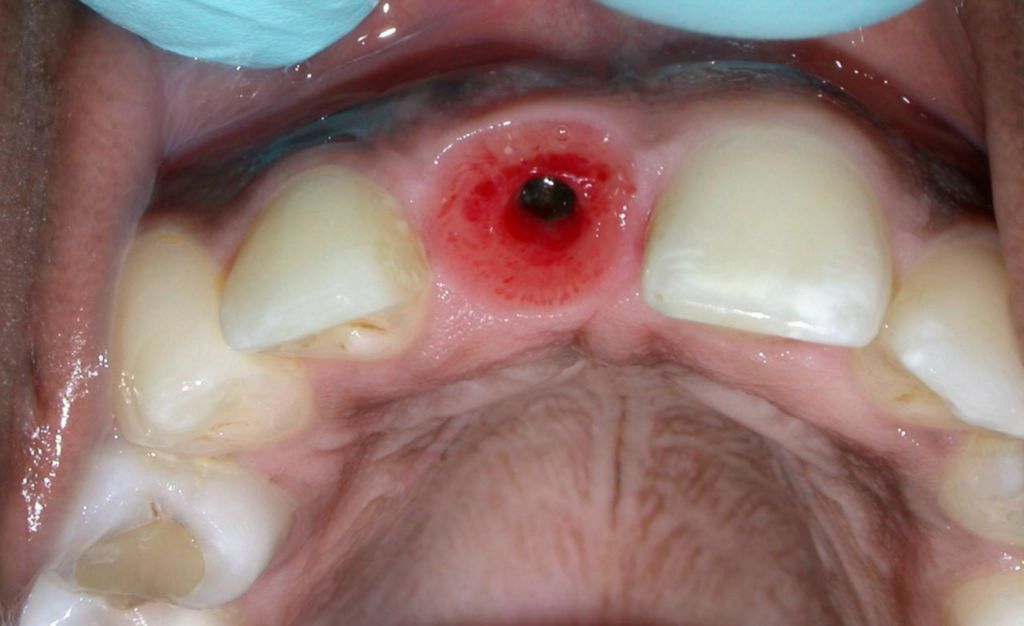

Single Dental Implant